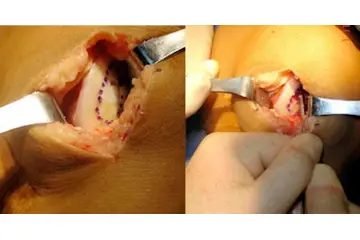

Tedavi Seçenekleri Burun kıkırdak eğriliği tedavisi, hastanın semptomlarına ve durumun ciddiyetine bağlı olarak değişiklik gösterir. Tedavi yöntemleri şunlardır: